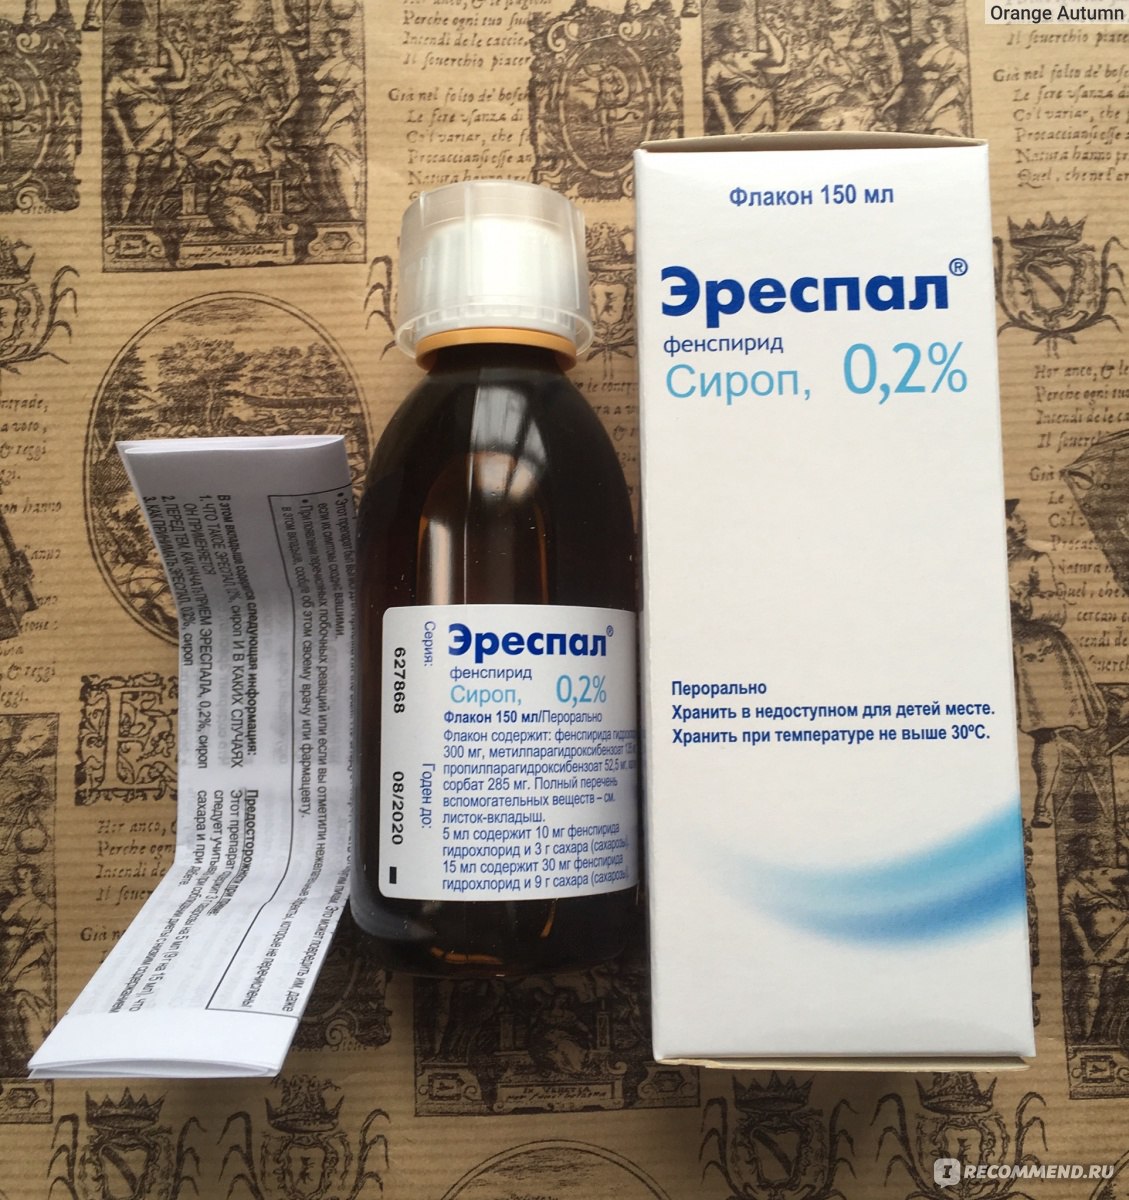

Эреспал детям